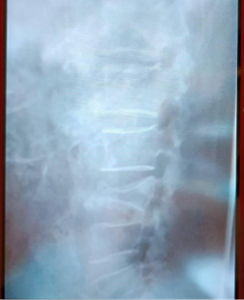

● 3月8日(整形外科・レントゲン)

• L3・L4横突起骨折 を確認

• この時点では圧迫骨折の診断はなし

● 3月17日(整形外科・CT)

• ここで初めて「腰椎3番の圧迫骨折」確定診断